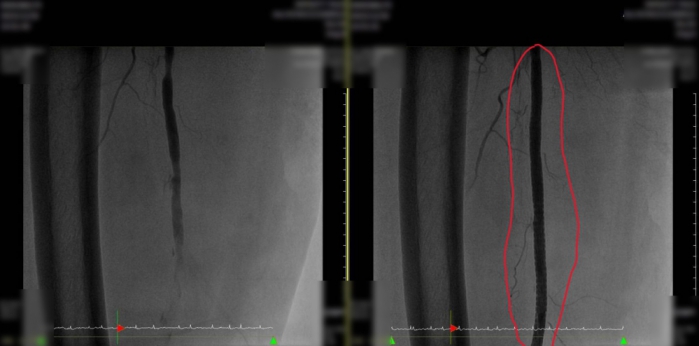

阿祖住院隔日,送進導管室進行氣球擴張血管成型術,但左側股動脈有超過25公分完全阻塞和嚴重鈣化,始終無法有效打通血路,阿祖的左下肢冰冷疼痛依然存在,賴主任即進行左下肢動脈繞道手術,考量年紀大,慢性疾病又多,屬中度以上手術麻醉風險,但確定阿祖和家人意向後,會診心臟科和麻醉科,作術前評估,研判心臟和麻醉風險中度,家屬信任賴主任的手術。

手術過程順利,但難度頗高,左側股膕動脈粥狀硬化和鈣化程度嚴重,需要先做動脈內膜切除,其次左側膕動脈深度至少10公分深,血管縫合不易,動脈因栓塞發炎,周邊組織嚴重沾黏。經四個小時細心手術,過程順利,左足冰冷感及疼痛,在術後第一天有顯著改善。